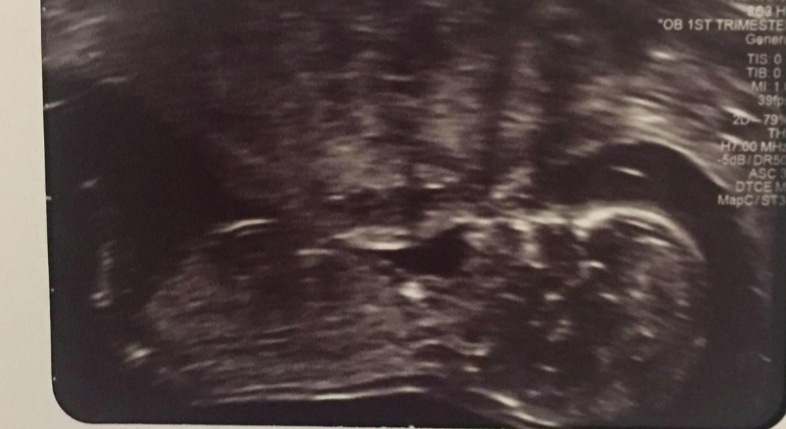

Not the best pics from scan but baby is 12 weeks 6 days.

It's our first baby and so excited!

The third pic baby is upside down